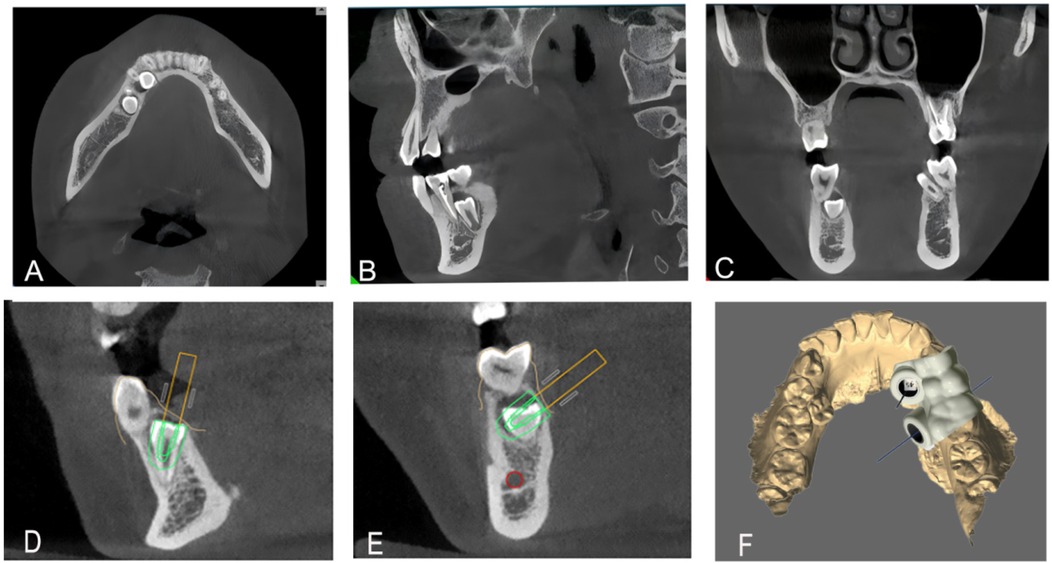

Minimally Invasive Removal of Impacted Supernumerary Teeth Using Digital 3D-Printed Surgical Guides: A Case Series

The surgical management of impacted supernumerary teeth (ST) remains challenging because of their hidden position and close proximity to vital anatomical structures. These guides offered accurate intraoperative guidance and minimized both bone removal and soft-tissue dissection. A standardized digital workflow that integrates cone-beam computed tomography (CBCT) and intraoral scans was employed to create patient-specific guides that precisely dictated the osteotomy location. The guides provided critical intraoperative guidance and minimized the extent of bone removal and soft tissue dissection. This accurate and focused approach contributed to observed reductions in postoperative discomfort and swelling, supporting an overall favorable recovery profile in all cases. The application of 3D-printed surgical guides enables a highly precise and minimally invasive approach for the removal of impacted ST, thereby improving postoperative recovery. Furthermore, this technique shows considerable potential for broader application in oral and maxillofacial surgery by ensuring precise localization, reducing complications, and enhancing operative efficiency.